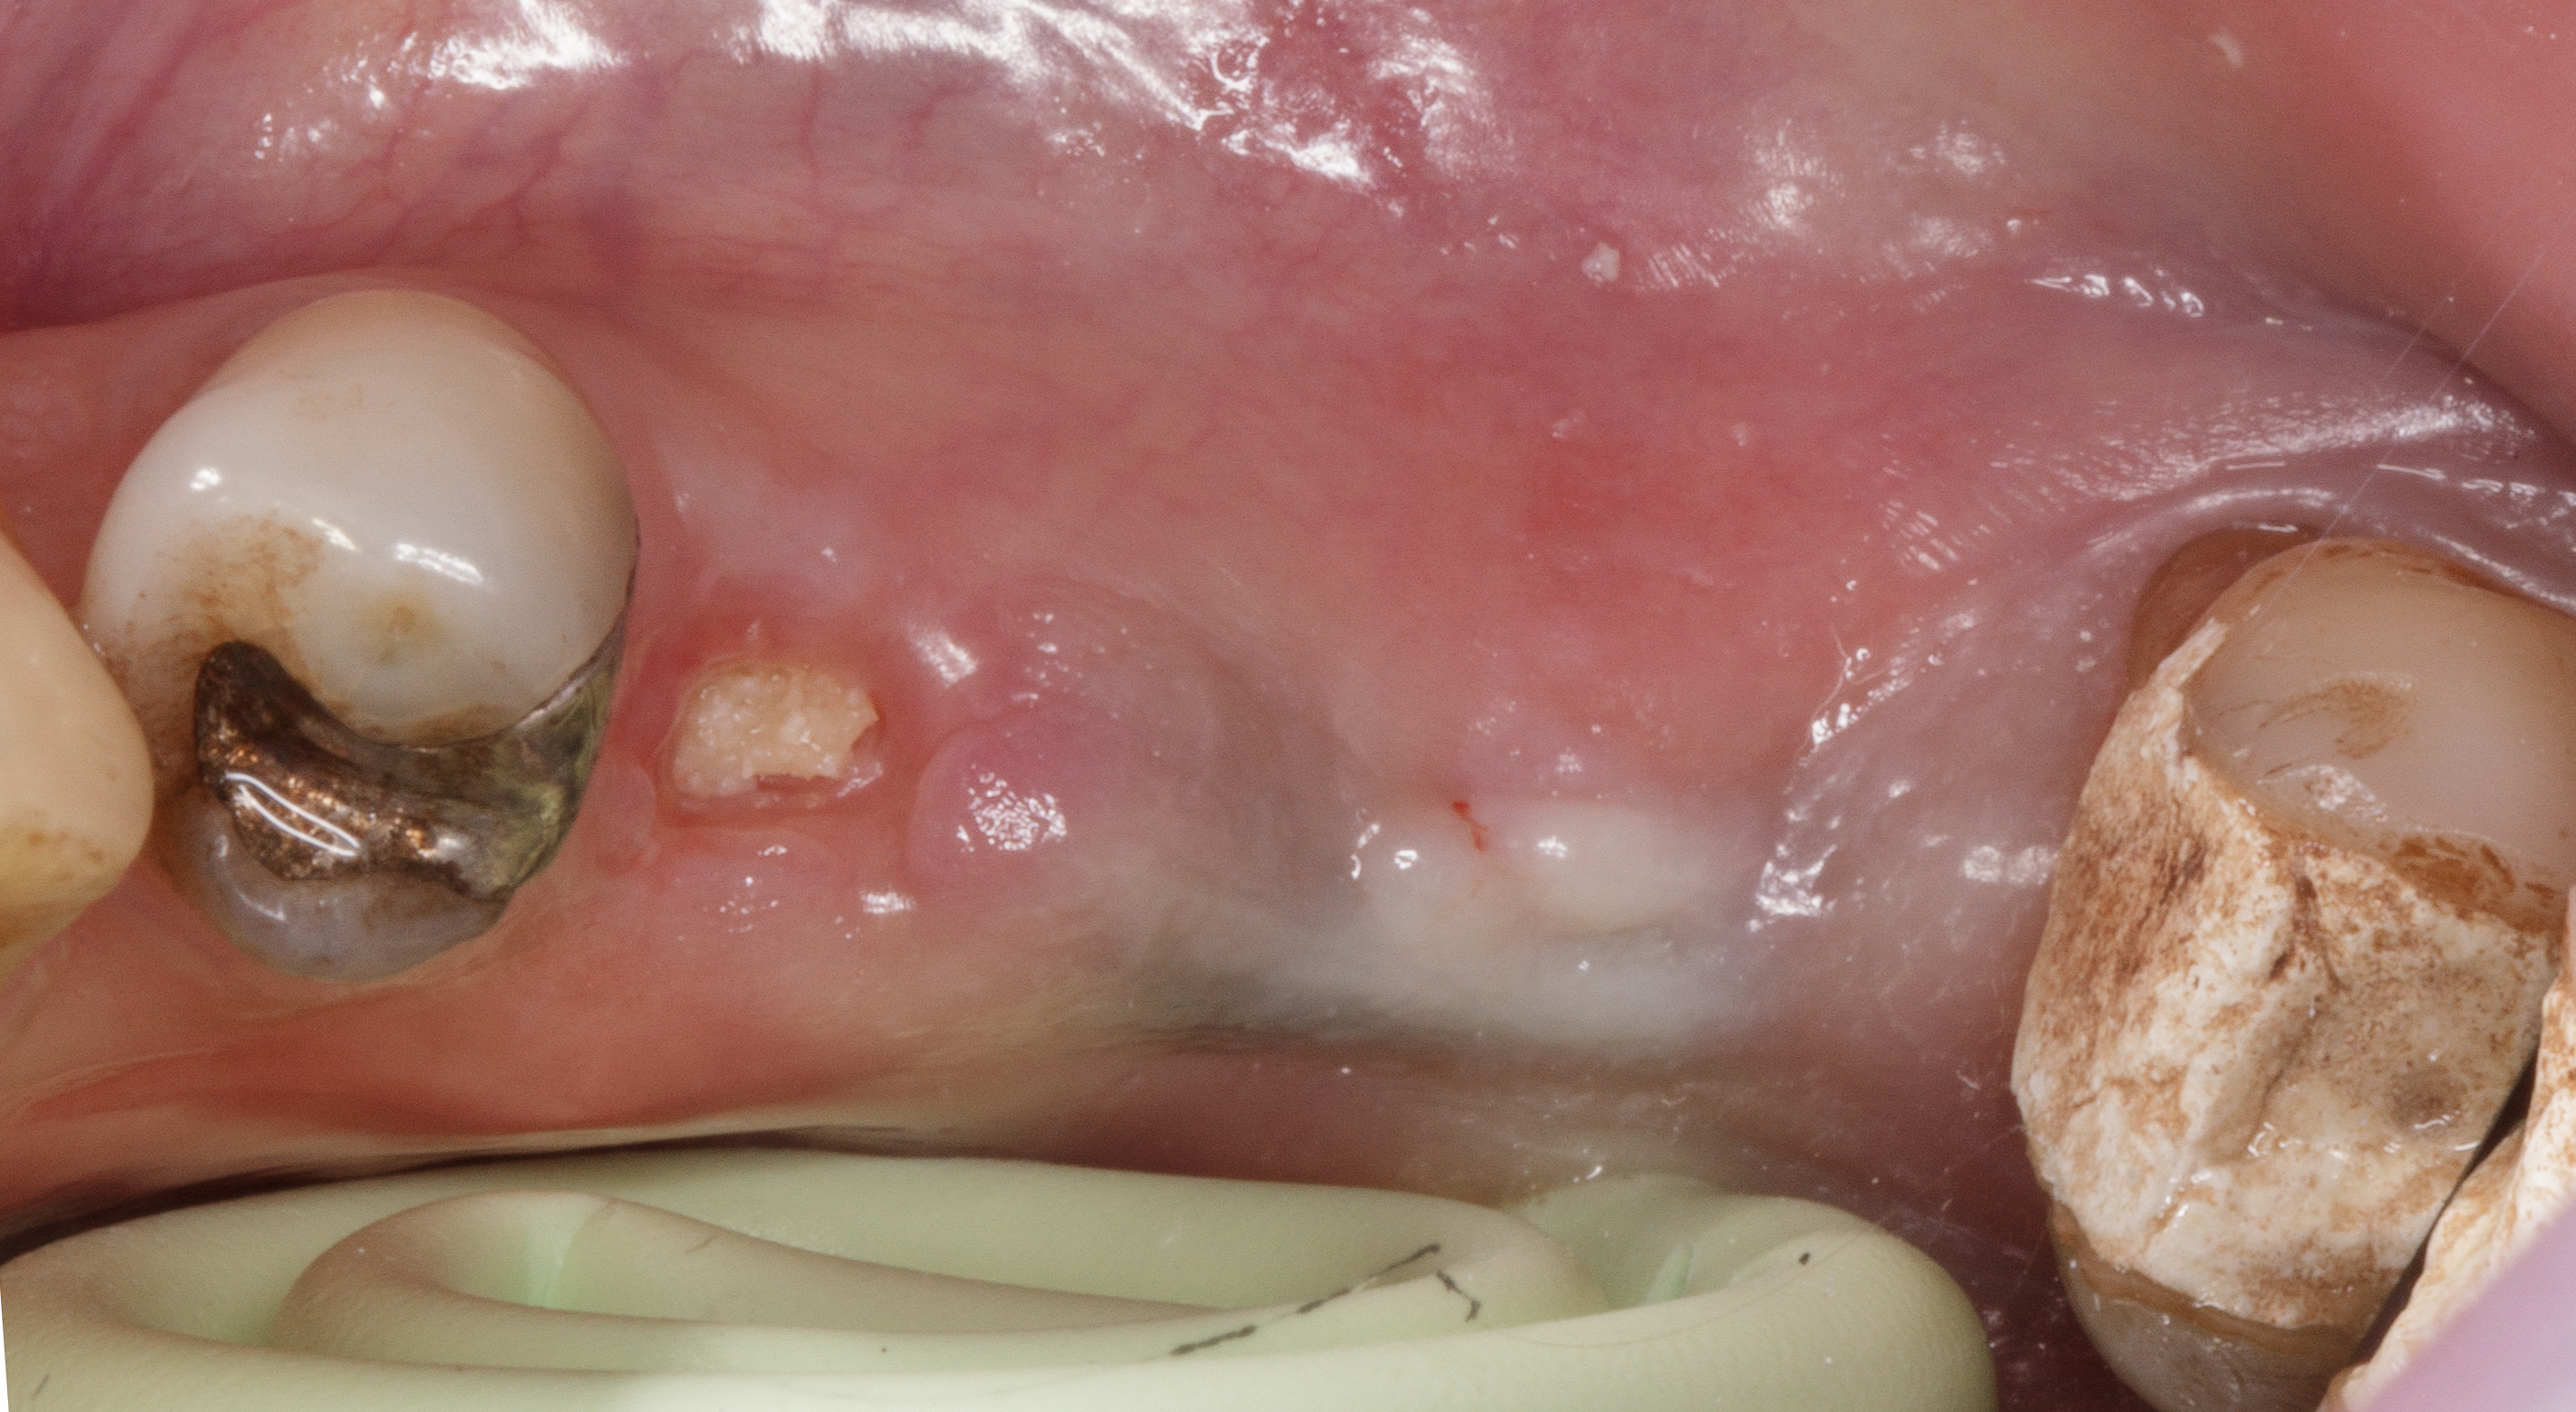

Dopo la rimozione della sutura normalmente si procede con un piano di mantenimento parodontale e di controllo sino a completa integrazione del graft osseo, ma il paziente, a soli 25 giorni dall’intervento di preservazione alveolare in posizione 4.5, richiede l’inserimento di un impianto in posizione 4.6.

Questa situazione, anche se non prevista dal piano di trattamento iniziale, consente di valutare clinicamente a cielo aperto il pattern di guarigione ossea e connettivale nel primo mese dopo l’intervento rigenerativo post-estrattivo (Figura 12).

Dopo aver inciso un lembo mucoperiosteo senza incisioni di scarico verticali, si vede la zona oggetto di estrazione omogeneamente riempita da tessuto osteoide in fase di maturazione.

Una gran parte della membrana riassorbibile posta all’interno dell’alveolo è ancora ben evidente e adesa al tessuto in fase di maturazione.